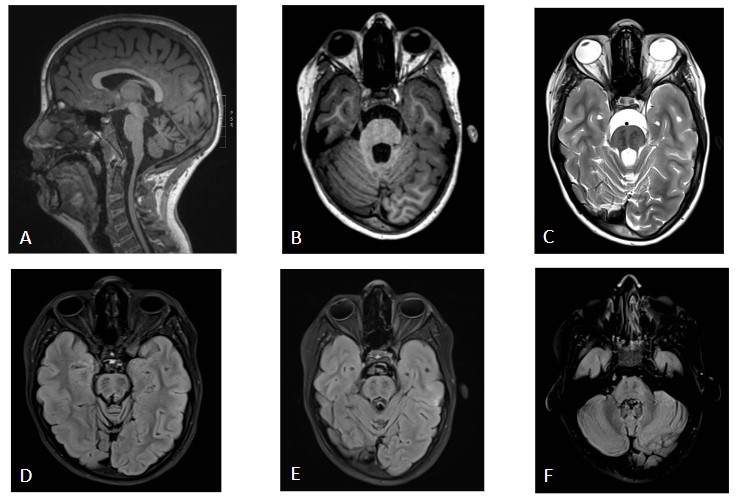

A (T1 sagital) y B (T1 axial): Atrofia de vermis superior. Discreta atrofia, de menor entidad, cerebelosa superior así como pontina y en médula cervical.

C (T2 axial), D, E y F (T2 FLAIR axial): Hipointensidad protuberancial bilateral de aspecto atigrado con morfología de tracto. Atrofia protuberancial.

Los hallazgos en RM revelan atrofia cerebelosa más marcada en el vermis superior asociada con atrofia espinal. Estos hallazgos distinguen a la ARSACS de otros tipos de atrofias cerebelosas autosómicas recesivas, como la ataxia de Friedrich o la ataxia telangiectasia. Se ha descrito típicamente un patrón atigrado de la protuberancia (hipointensidad lineal en T2-WI). Existen otros hallazgos comunes pero menos específicos, tales como: atrofia del vermis inferior, atrofia superior de la medula espinal, atrofia del hemisferio cerebeloso, hiperintensidades T2 talámicas , adelgazamiento del cuerpo calloso.